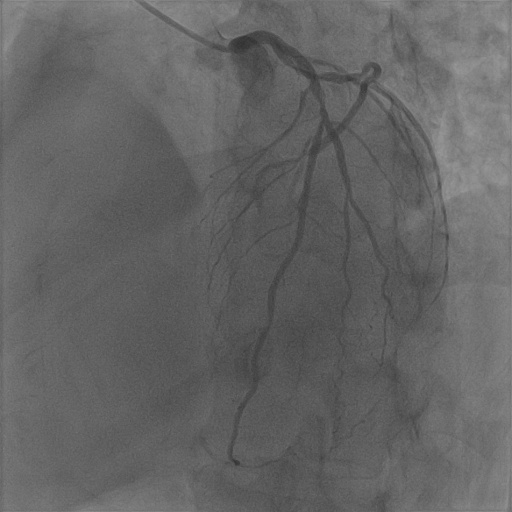

| Image | Ground truth | Video frame | Ground truth | Video frame | Ground truth |

| XCAD [33] | CADICA [19] | Our XACV dataset | |||

4.1 XACV Dataset

We collect 111 complete records of coronary artery X-ray videos, encompassing the injection, flow through the blood vessels around the heart, and dissipation of the contrast agent. Subsequently, we establish the XACV (X-ray Angiography Coronary Video) dataset. Each video consists of varying numbers of high-resolution coronary artery X-ray images. We invite experienced radiologists to annotate the vascular regions, focusing on one or two frames where the contrast agent is most prominent in each video. The XCAD dataset contains only a single image, and the CADICA video dataset does not provide corresponding ground truth. Therefore, in the following experiments, we conduct all the analyses on our collected XACV dataset and the corresponding GT for each sequence. In Figure 5, we show that compared to other publicly available datasets, XCAD [33] and CADICA [19], our dataset exhibits finer annotations in the vascular regions, providing an advantage for future related tasks. The development and use of our dataset have been approved by our institution’s IRB.